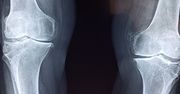

Osteoporoza - klasyfikacja, diagnostyka, profilaktyka, leczenie